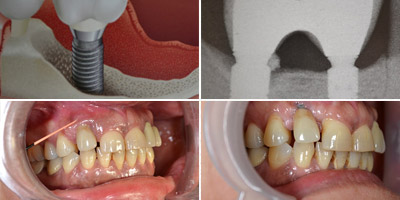

Parodontologia e implanto-protesi